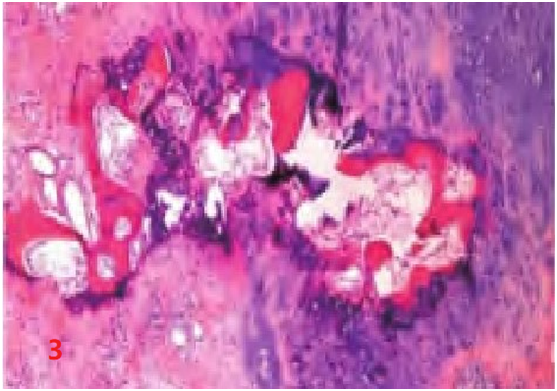

目前应用的软骨肉瘤分级系统将其分为3级[2],Ⅱ级以及Ⅲ级软骨肉瘤与内生性软骨瘤通过组织形态学鉴别不难,但Ⅰ级软骨肉瘤与内生性软骨瘤形态学具有相似性,通过细胞学难以鉴别,主要鉴别依据来源于二者的生物学行为。与软骨肉瘤相比较,内生软骨瘤呈非浸润性生长:①“软骨岛”形成(图3)。低倍镜下,肿瘤性软骨形成相对独立的软骨结节,由正常或相对正常的宿主板层骨和骨髓组织分隔。②呈现良性软骨瘤独特的包绕方式,即良性肿瘤性软骨周围部分或完全由宿主骨包绕。软骨肉瘤则可以侵入骨髓腔,可完全替代骨髓组织,并见其浸润并包围正常宿主骨小梁[3]。